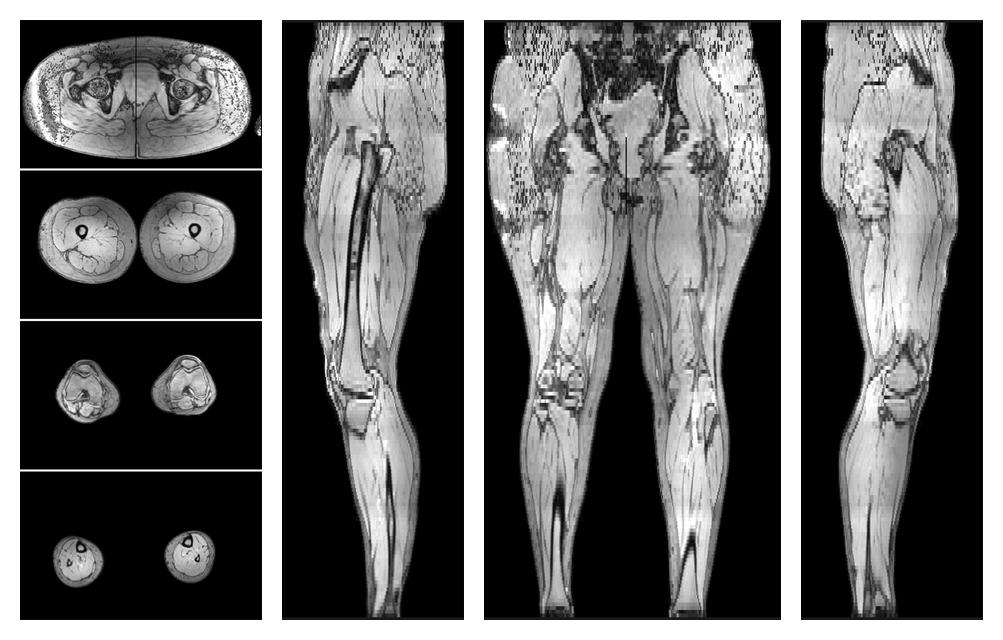

• Automated muscle and bone segmentation.

Overlay of automated muscle segmentation labels on dixon water image.